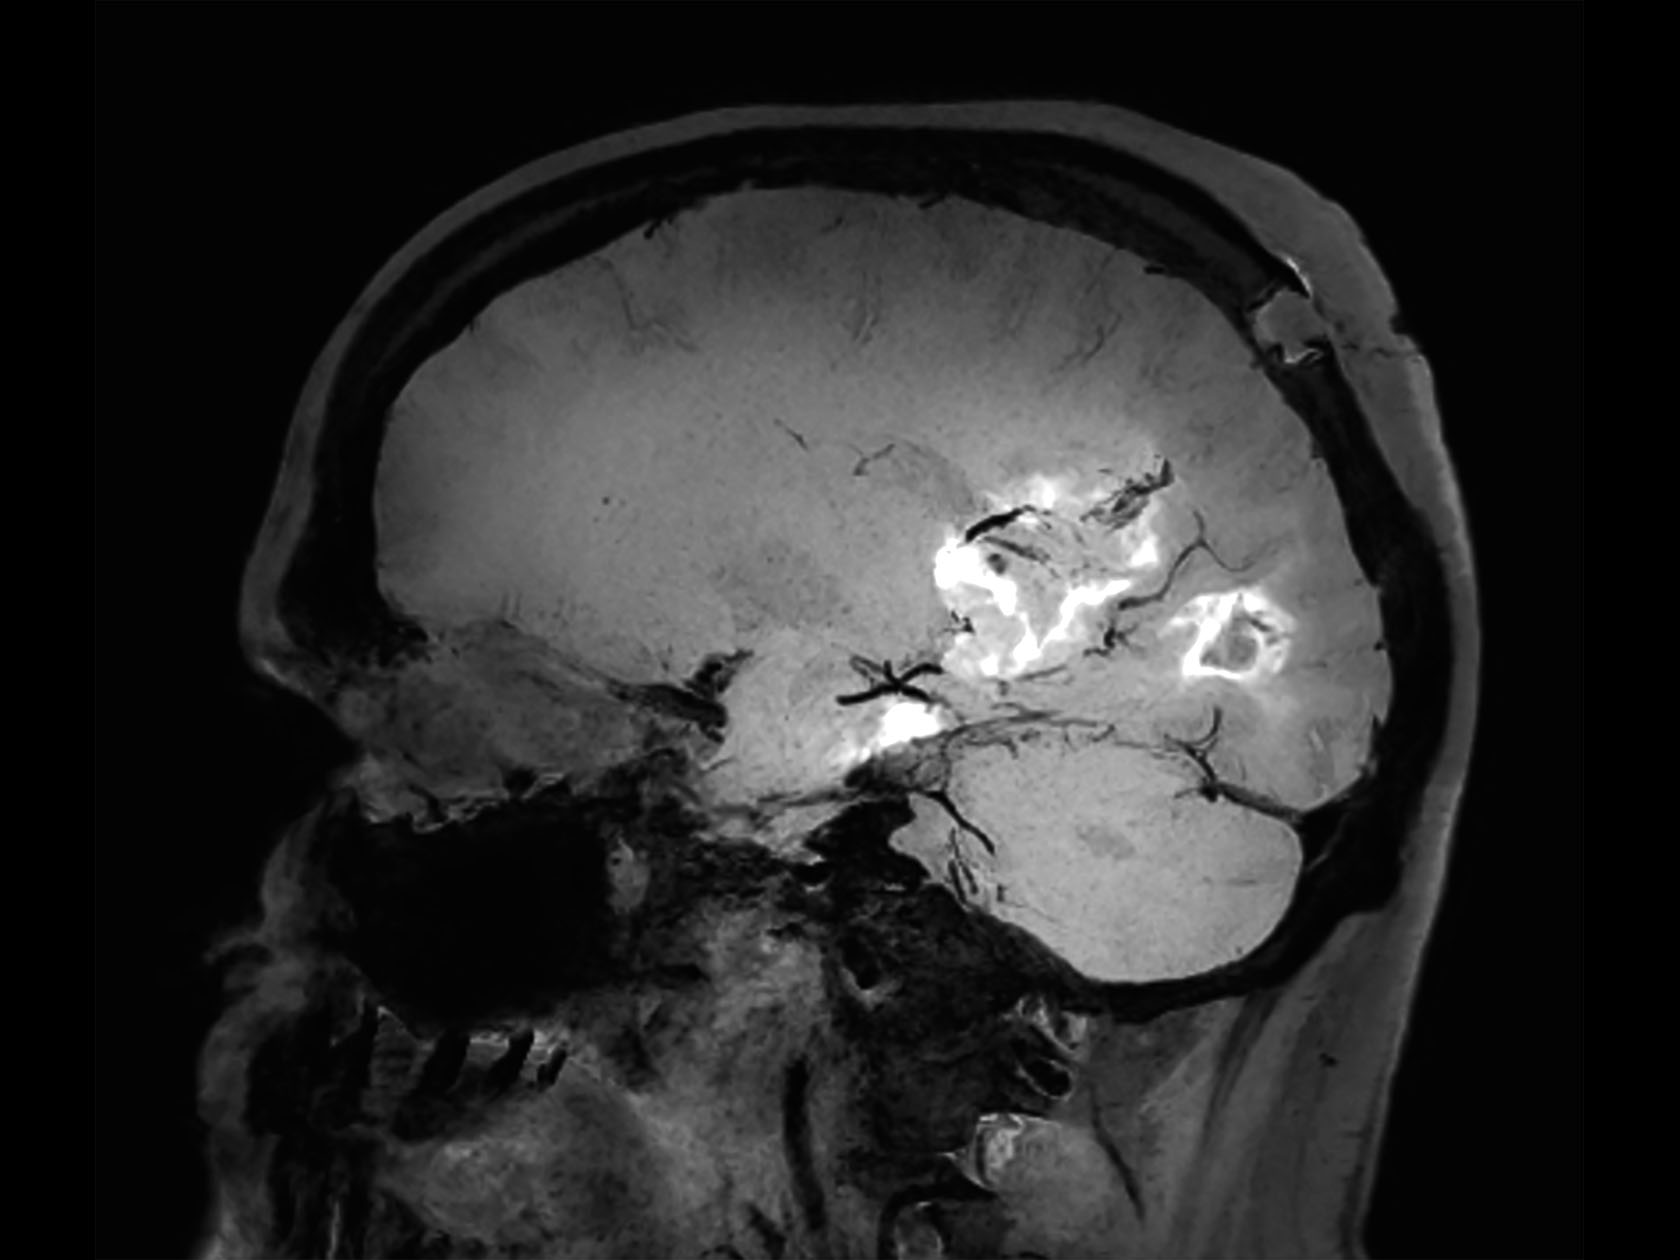

Sagittal 3D T1w FFE mDIXON (post-gado)

-

Sagittal T1w FFE (post-gado)